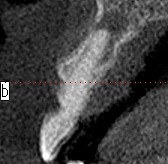

正中口蓋嚢胞。 2年後自然消失。| |広島市安佐南区の歯科医院 正中口蓋嚢胞。 2年後自然消失。 トップ お知らせ・ブログ 正中口蓋嚢胞。 2年後自然消失。 正中口蓋嚢胞。 2年後自然消失。 Web診療予約 初めての方へ 選ばれ続ける理由 院内設備について 歯が痛いしみる一般歯科 歯がぐらぐらする歯周病 健康な歯を保ちたい予防歯科 子供の虫歯予防をしたい小児歯科 銀歯をセラミックに審美歯科 白い歯を目指しませんか?ホワイトニング 矯正専門医がいるので安心矯正歯科 抜けた歯を補いたいインプラント・入れ歯 医院案内 スタッフ紹介 メリィハウス歯科クリニックオフィシャルホームページ ラベンダー歯科クリニックオフィシャルホームページ お知らせ・ブログ ホーム 診療科目 一般歯科 歯周病治療 予防治療 小児歯科 審美治療 ホワイトニング 矯正歯科 入れ歯・インプラント マウスピース矯正 初めての方へ 院長・スタッフ 設備紹介 医院案内・アクセス メニューを閉じる